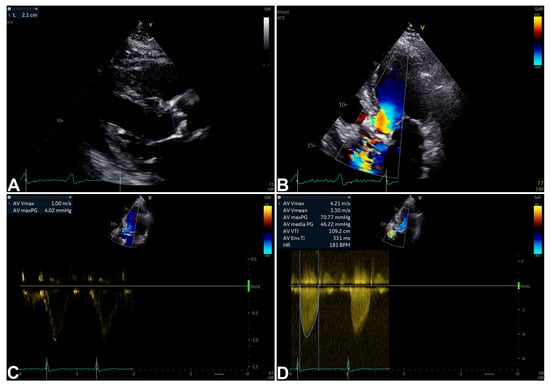

3. Echocardiography for Isolated Severe Aortic Stenosis Assessment and Characterization

| Peak velocity (m/s) | ≤2.5 | 2.6–2.9 | 3.0–4.0 | ≥4 | - Direct measurement. - Strong predictor of clinical outcome. | - Flow-related. - US beam parallel alignment-related. |

| Mean gradient (mmHg) | None | <20 | 20–40 | ≥40 | - Units comparable to invasive measurements. | - Flow-related. - US beam parallel alignment-related. |

| AVA (cm2) | None | >1.5 | 1.0–1.5 | <1.0 | - Effective orifice area measurement. - Frequently feasible. - Relatively flow-related. | Measurement error more likely. |

| iAVA (cm2/m2) | None | >0.85 | 0.60–0.85 | <0.60 | - Effective orifice area measurement. - Frequently feasible. - Relatively flow-related. - More accurate than AVA. | Measurement error more likely. |

| Velocity ratio | None | >0.50 | 0.25–0.50 | <0.25 | - Less variability than AVA (Doppler-only required). | - Limited longitudinal data. - Ignores LVOT size variability. |